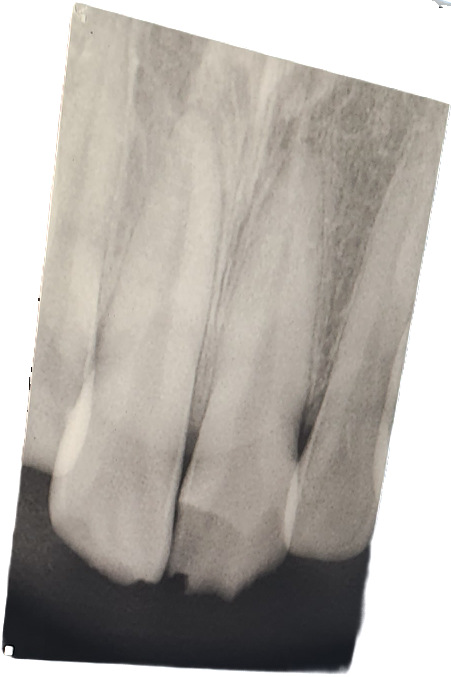

신경이 노출되어보이지는 않습니다.

제법 많이 부러졌습니다. 시린 증상이 있다면 신경치료해야 할 가능성이 높습니다. 저 정도로 부러진 경우 만약 신경치료 안하면 스스히 신경이 괴사되니 미리 신경치료하는 것이 좋습니다.

신경이 직접적으로 노출된 것으로 보이지는 않습니다. 증상을 좀 지켜보는 것이 좋고 만약 그 사이에 색이 변하거나 하면 신경치료는 어쩔 수 없이 해야 합니다. 외상 치아 체크는 2주후에 한번 더 하는 것이 좀 더 적절하겠습니다

사진으로만 봤을 경우에는 치아가 부분적으로 파절된 것으로 보입니다 신경의 통증이 없다면 신경까지 노출이 되지 않았을 가능성이 높기 때문에 크라운 등의 보철 치료로 치료를 수복할 수 있습니다.

치아가 너무 시리고 통증이 심하다면 신경치료를 한 다음에 크라운 치료를 해주는 것이 좋습니다